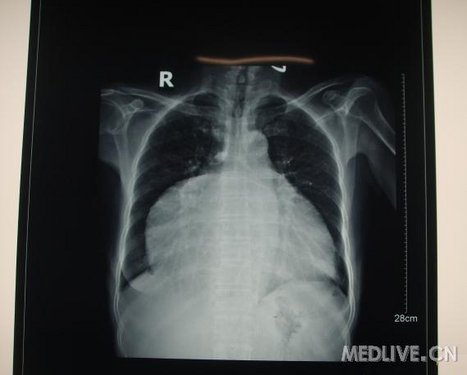

术后当天胸片提示:心影明显变小。

http://webres.medlive.cn/upload/000/060/746